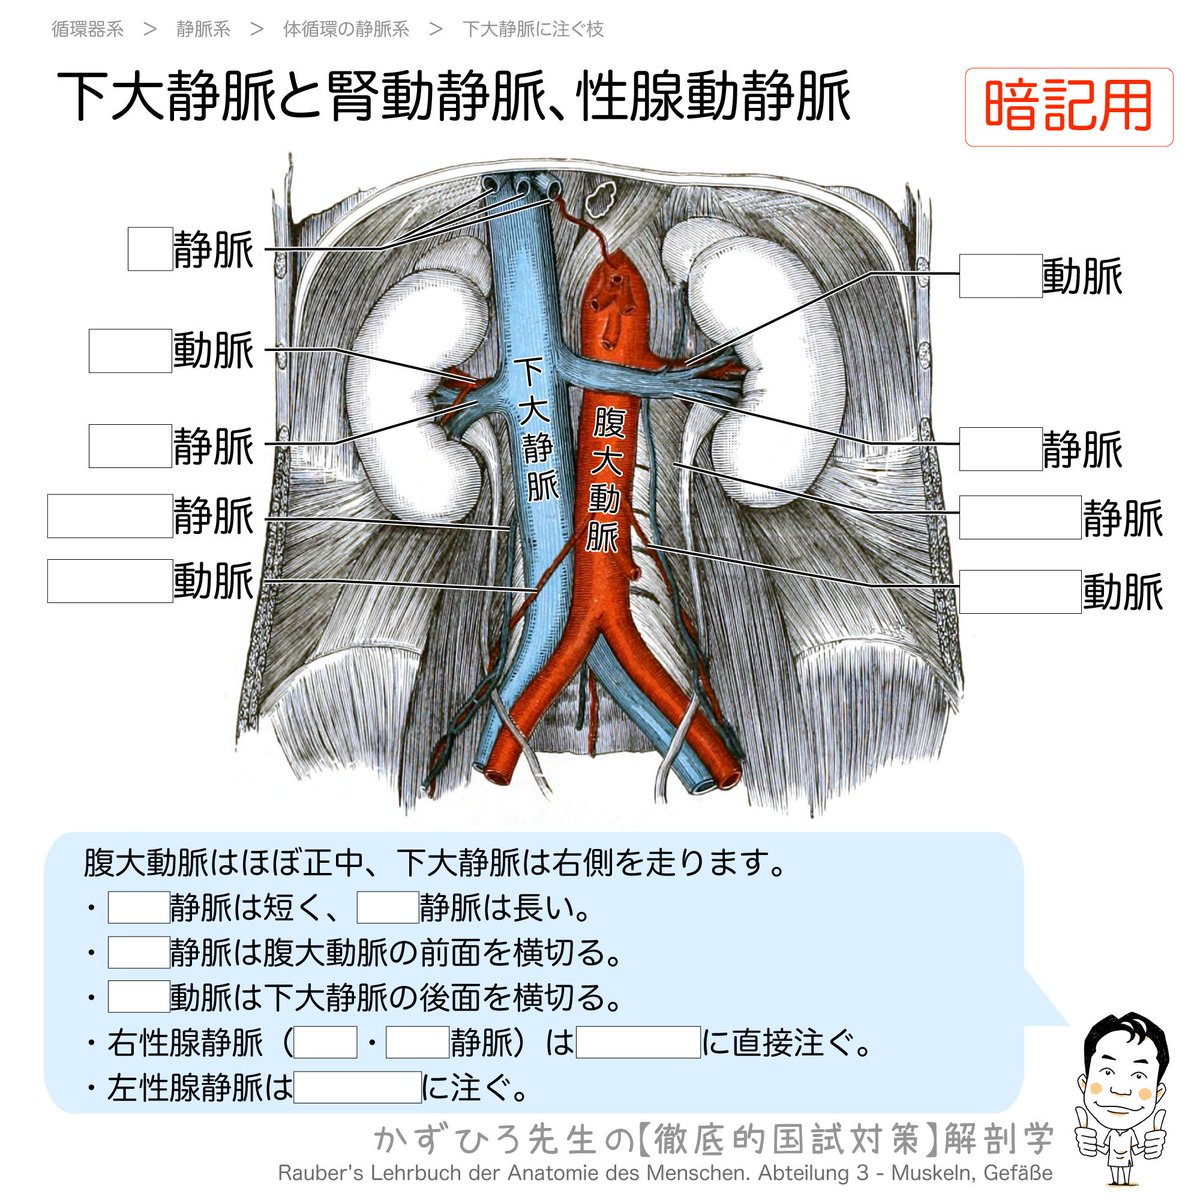

CT・MRI画像解剖ポケットアトラス 第4版 2巻 胸部・心臓・腹部, 黒澤一弘(かずひろ)解剖学IT教育・指圧師・ラダック on X,

黒澤一弘(かずひろ)解剖学IT教育・指圧師・ラダック on X, 乳様突起部 - e-Anatomy - IMAIOS,